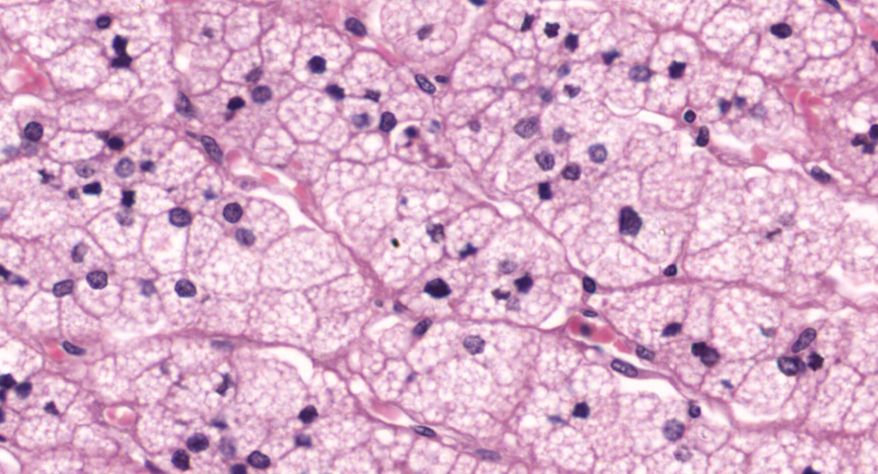

低倍镜观察:1. 被膜:由薄层结缔组织组成。2. 实质:由许多大小不等的滤泡构成。滤泡壁是单层立方上皮细胞,滤泡腔内充满粉红色匀质胶状物,滤泡之间的结缔组织内有丰富的血管。高倍镜观察:1. 滤泡:滤泡壁的单层滤泡上皮细胞一般呈低柱状或立方状,胞质着浅色,细胞核呈圆形。滤泡腔内充满了粉红色匀质胶质。2. 滤泡旁细胞:体积较大,呈圆形或椭圆形;细胞核较大,呈圆形,着色较浅,细胞质染色也较浅。细胞或嵌在滤泡壁上或成团分布于滤泡之间。3. 间质:由结缔组织组成。位于滤泡之间。其中含有丰富的毛细血管及三五成群的滤泡旁细胞。

2.滤泡

3.滤泡上皮细胞

4.胶质

5.滤泡旁细胞1

7.滤泡旁细胞2